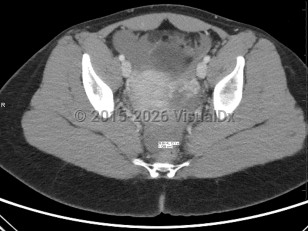

The term ectopic pregnancy refers to implantation of a developing blastocyst at any location outside of the endometrial cavity. Ectopic pregnancies can be found in the cervix, cornua, fallopian tubes, ovaries, or a prior cesarean delivery scar, or, more rarely, attached to the abdominal lining, bowel, or other viscera. The most common location is the fallopian tube, specifically the ampulla, which accounts for about 70%-80% of cases, followed by the isthmus and fimbria. Prevalence is estimated at 25 in 1000 pregnancies, with fewer than 200 000 cases in the United States per year. It is a medical emergency.

Ectopic pregnancies are, by definition, nonviable. If left untreated, they may cause their containing structure (eg, fallopian tube, cornua, scar) to rupture, leading to acute blood loss and subsequent morbidity and possibly death. Black women are nearly 7 times as likely as White women to die from the condition due to health disparities and access to care. Improved technology (biochemical markers, ultrasonography, etc) has enabled health care practitioners to identify a majority of ectopic pregnancies before rupture to reduce associated morbidity and mortality.

Ectopic pregnancies are found in reproductive-age patients. Risk factors include prior ectopic pregnancy, history of endometriosis or tubal infection (pelvic inflammatory disease), pregnancy occurring in the setting of current use of a progesterone intrauterine device (IUD), history of tubal surgery, advanced maternal age (aged 35 years or older at time of due date), and tobacco use. It is also important to note that over 50% of all patients diagnosed with an ectopic pregnancy have no known risk factors.

Presentation can vary. Patients may present with a positive home pregnancy test and unilateral lower quadrant pain that is often sharp / stabbing in nature. Some will present after tubal rupture and be hemodynamically unstable. Others may present with only vaginal spotting and be unaware they are even pregnant. Therefore, one must have a high index of suspicion when a patient arrives with a positive pregnancy test and symptomatology. As many as 18% of women presenting to the emergency department with first-trimester bleeding, pain, or both will be found to have an ectopic pregnancy.